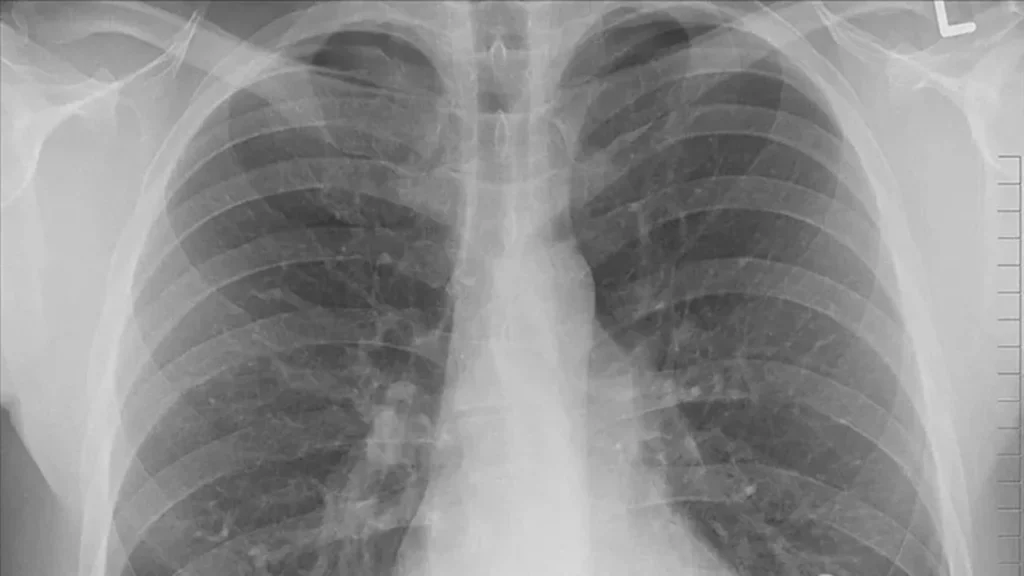

Hangi Testler Ve Muayene Yaklaşımı Öne Çıkar?

Uzman değerlendirmesinde şikâyet süresi, maruziyet öyküsü ve muayene bulguları önemlidir. Gerekli görüldüğünde akciğer filmi, solunum fonksiyon testi veya ileri görüntüleme gibi yöntemler kullanılabilir.